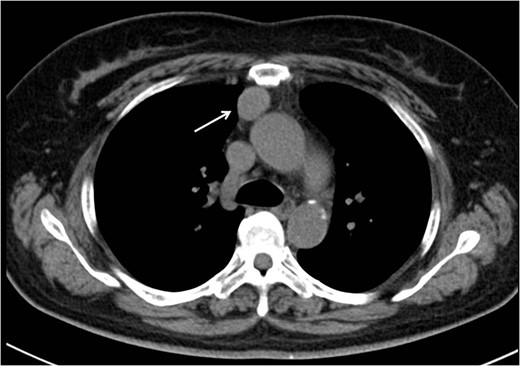

Follow-up CT performed 36 months after the operation revealed two pleural tumors located near the second and third ports (Fig. 2a and b). We suspected the pleural recurrence of thymoma and performed a second operation. Initially, the operation was performed only by VATS with three ports. After removing the severe adhesion between the lung and chest wall, we were able to identify the two tumors. As with the extrapleural tumor, the tumors arose from the intercostal space. Their surfaces were covered with parietal pleura with partial irregularity (Fig. 3). There were no other recurrent findings in the thoracic cavity. Given these findings, we diagnosed these tumors as port-site implantations after the first VATS.

In the operative findings, the tumors were found to have arisen from the intercostal space, and their surfaces were covered with parietal pleura with partial irregularity.